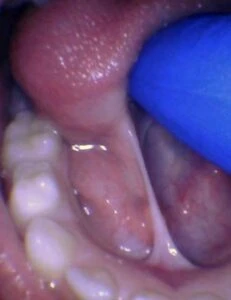

IMAGES OF TONGUE- AND LIP-TIES

Spectrum of lip restriction in a child

Spectrum of tongue restriction in a child

Posterior tongue-tie in a child seen with lifting the tongue. The posterior or “hidden”tongue-tie can cause the same symptoms including nursing pain and poor weight gain, as a to-the-tip tie in a child